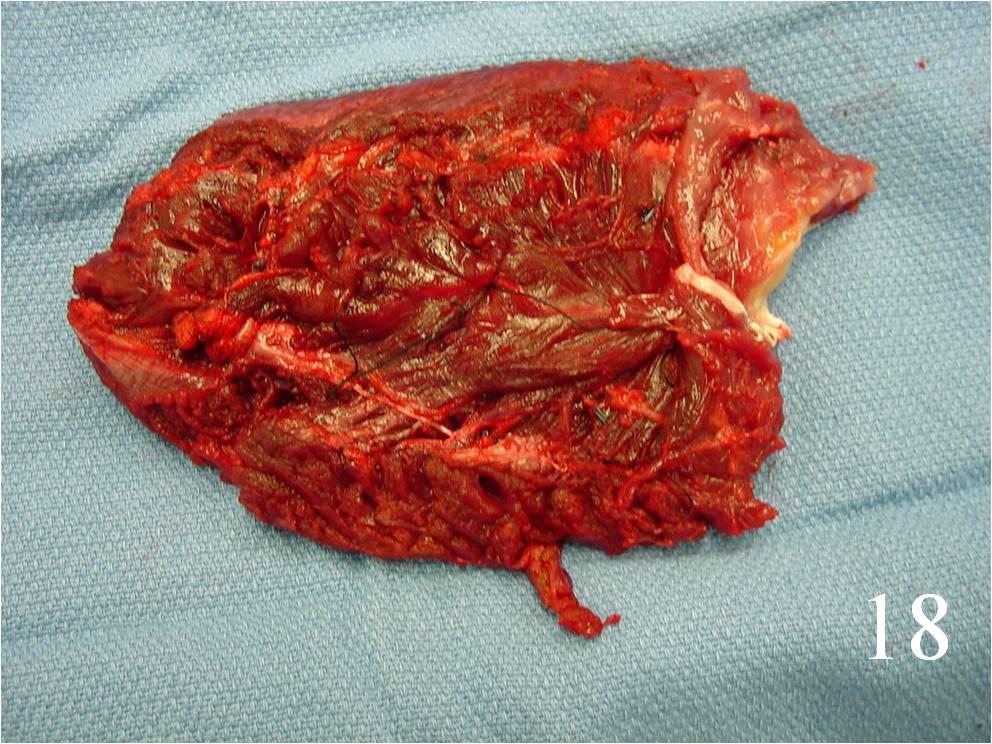

- Surgery: wide resection, chemotherapy, and possible radiation (Fig. 16-19)

Fig. 16-18: Intraoperative photograph shows a big rhabdomyosarcoma in the left calf. Photograph of a radical resection (Fig. 17) of the rhabdomyosarcoma to the calf. After the resection of the tumor (Fig. 18), multiple rotational flaps are performed to fill the dead space,